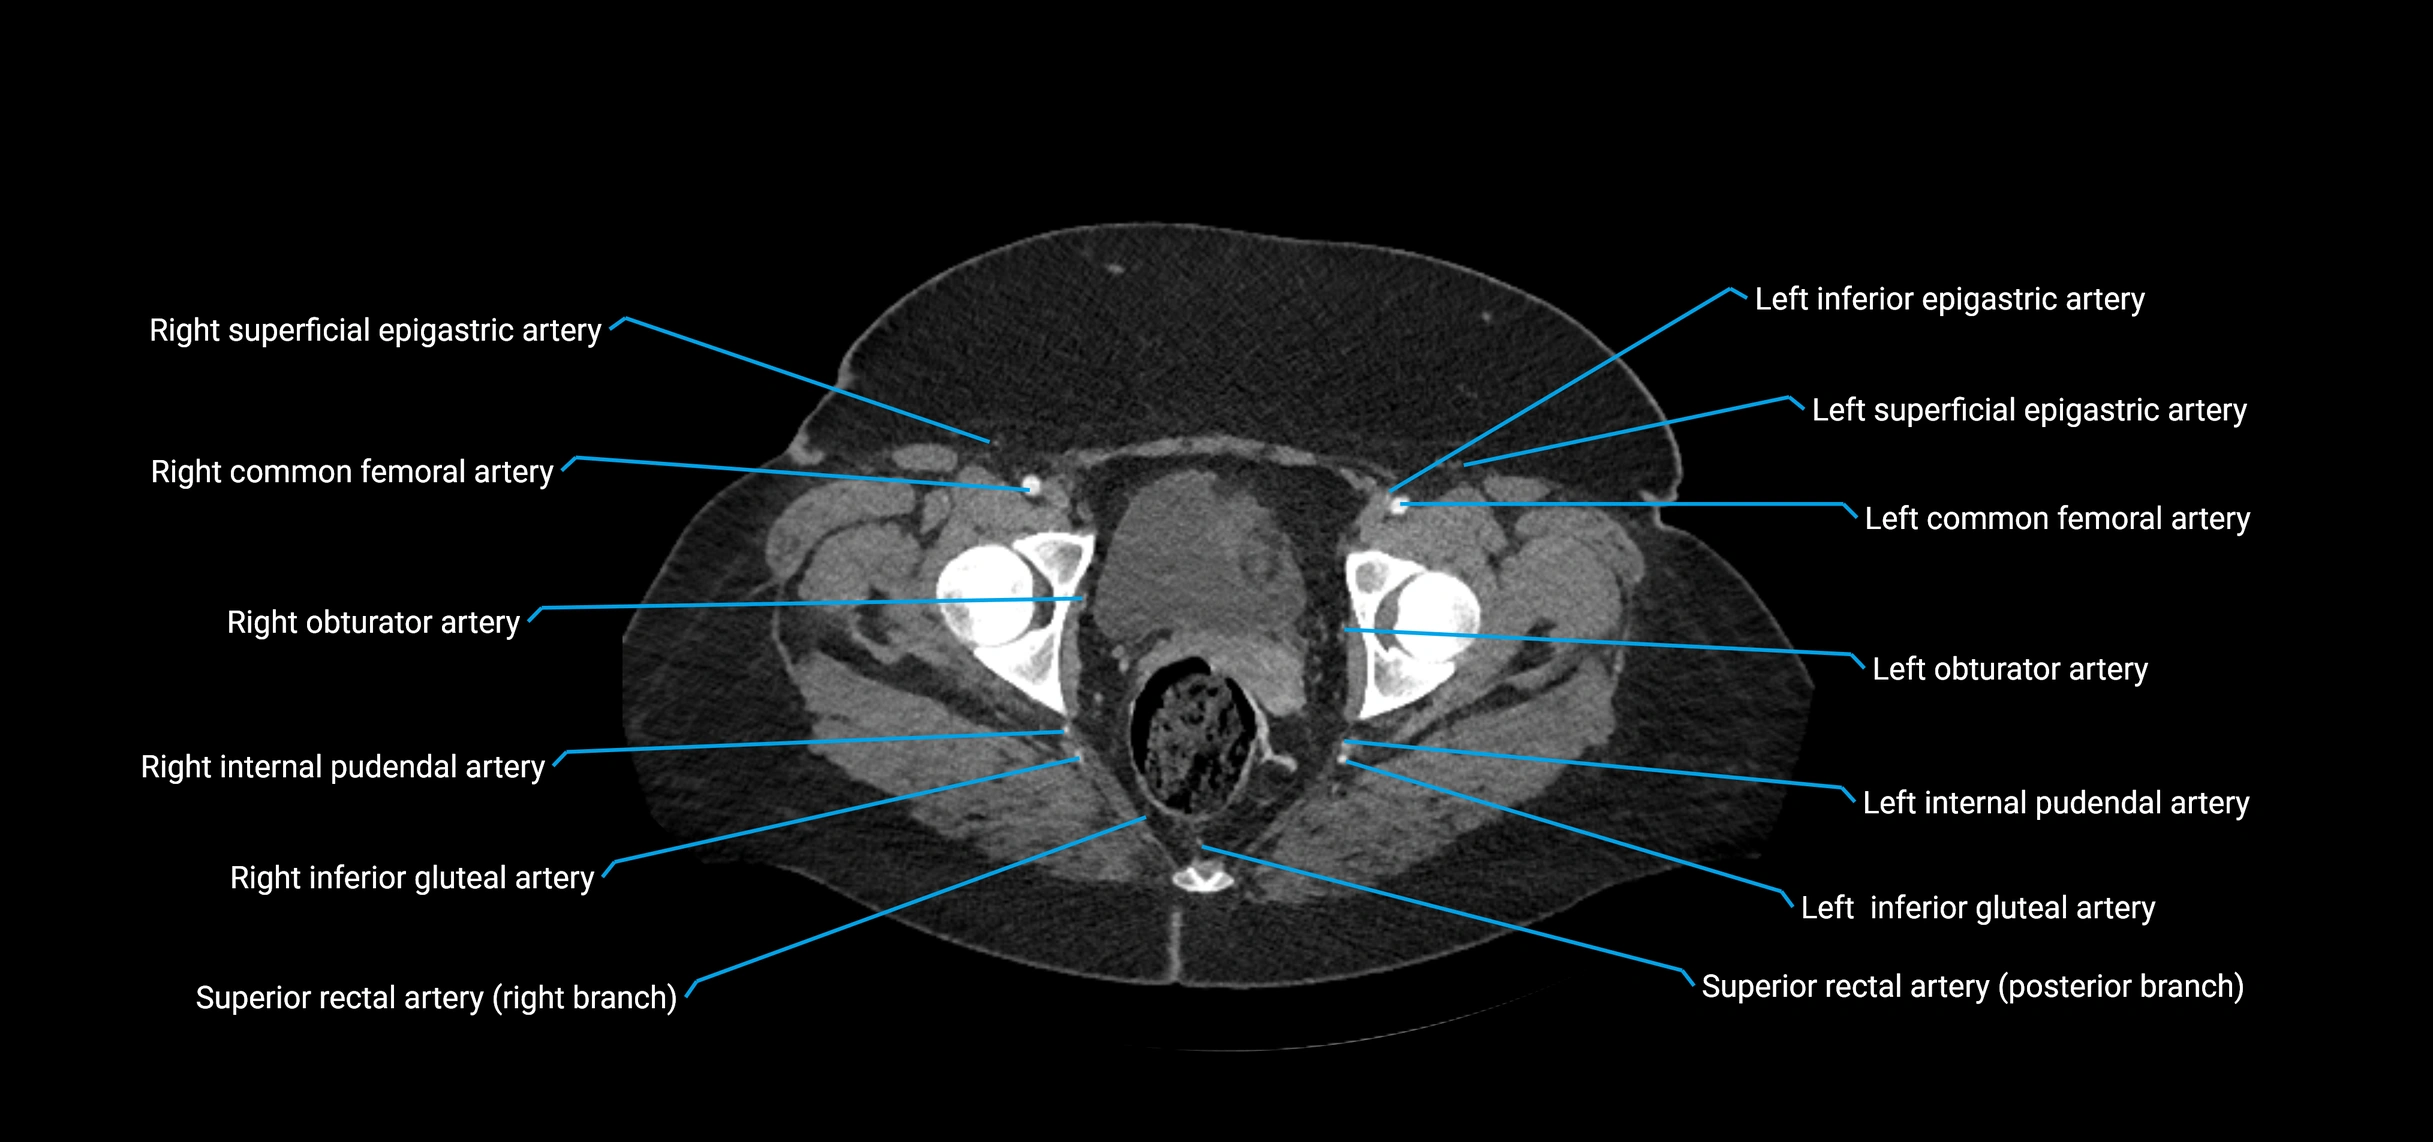

CT images

image

Contrast-enhanced CT (CTA):

• Gold standard for abdominal aortic imaging

• Provides excellent detail of lumen, wall, aneurysm, thrombus, and branch vessels

• Multiplanar and 3D reconstructions help in aneurysm measurement, stent graft planning, and dissection evaluation